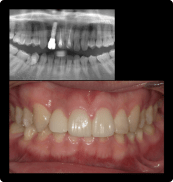

一番奥の入れ歯が噛みにくい方

BEFORE

AFTER

症例概要

年代・性別

50歳代 女性

主訴

奥歯で噛めない

治療内容

右下6番インプラント治療

治療期間

3ヶ月

治療のリスク

骨の状態によっては骨造成が追加で必要な場合があります。

メンテナンスやセルフケアの状態でインプラントの歯周病に犯される場合があります

治療費用

407,000円(税込)